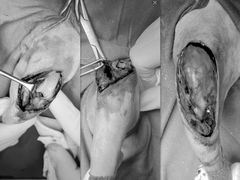

• 东莞宠友24H宠物中心医院·转诊夜诊·异宠(新河北路院)

• -东莞宠友24H宠物中心医院·转诊夜诊·异宠(新河北路院)

Arise_Tam | 24-04-10